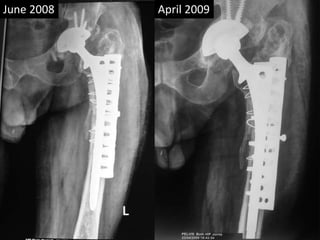

• 36 yrs Male

• Bilateral AVN hips

• AMP done 1988 rt side at the age of 36 yrs

• THR cemented done on left 1990 at the age of 38.

• Revision THR for shattered femur 2007

• Sciatic palsy

• Removal of Memmen plate and wires April 2009.

• Removal of THR Sept 2009.

• Metal fatigue 2012

• Last follow up Nov 2014.

Case Eighth

• Acetabular poly wear 2007.

• Sustained periprosthetic fracture with

shattered femur.

• Non cemented “Solution Hip” with Mammam

plate and circlage wires + bone grafting of

acetabulum.

• Sciatic nerve palsy.

• Persistent pain in hip

• Plate and wires removed in April 2009

• Pain in knee and hip persisting

• Solution hip system removed for suspected

low grade infection Sept. 2009.

• Serial x-rays showing broken amp in Jan 2012.

• Last follow up 2014.

• Sciatic nerve has partially improved.

June 2008 April 2009

April 2009